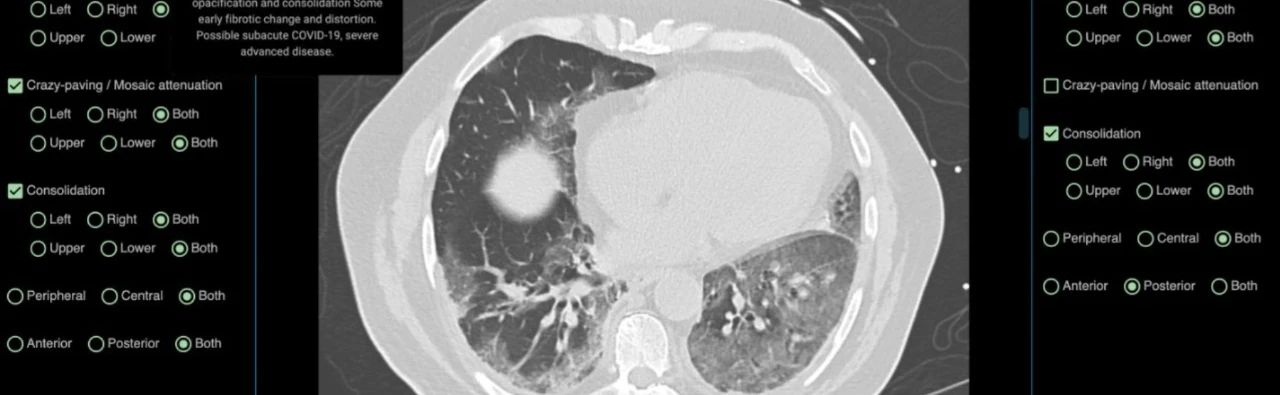

尽早诊断新型冠状肺炎对早期治疗和隔离至关重要。目前,肺部CT已被证明是诊断新型冠状肺炎的首要工具,但医生的CT读片技能可能需要长年累月的经验积累。由DetectED-X开发的名为CovED的辅助测试工具将帮助现有的医生及相关工作人员更快、更准确地诊断病例,并为更多有需要的人员及机构提供快速培训,从而获得完备的CT读片技能,其定制化的培训模块只需要1-2小时就可以生成。

CovED是一个全网开放且免费的平台,得到了全球医疗专家和领先企业的支持。借助CovED,临床医生可以通过真实的CT图像进行虚拟诊断并得到即时的反馈,查看虚拟诊断中产生的所有错误。系统还会按照业界标准为其打分,以此帮助使用者评估自身表现。随着时间的推移,诊断难度也会相应增加。

感染COVID-19 CT图

目前,CovED平台上使用的是来自澳大利亚和欧洲合作者的新型冠状肺炎病例的CT图像。“WHO呼吁全球团结起来应对COVID-19,我们非常感谢合作伙伴GE 医疗、Volpara、世界继续教育联盟(WCEA)和亚马逊的支持,使这个世界级的平台能被建立起来,并快速响应新型冠状肺炎的疫情发展。” Brennan教授说。